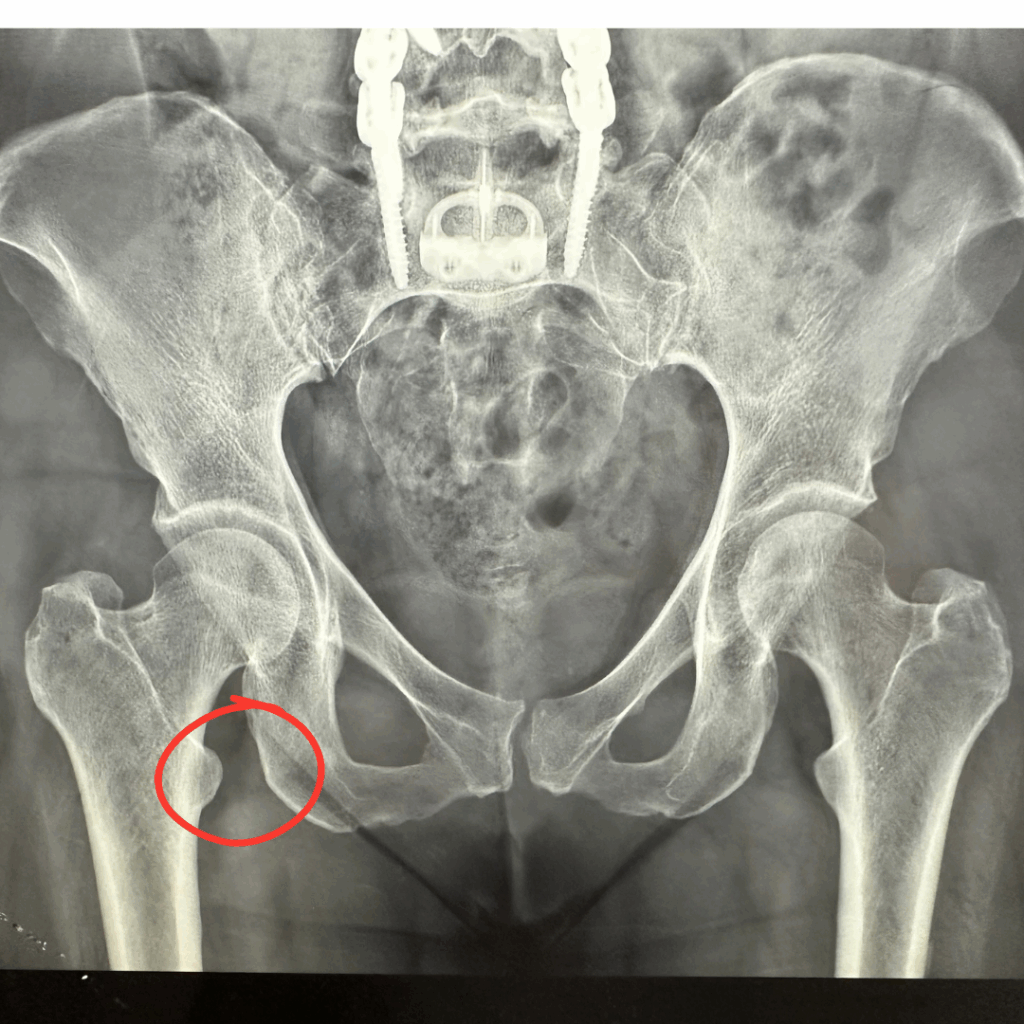

De nome parecido com o Impacto Femoroacetabular (IFA), porém bastante diferente nos seus sintomas e tratamentos, o impacto isquiofemoral (IFI) é uma condição rara que pode causar dor profunda na parte de trás do quadril ou na região da nádega. Ele acontece quando há um espaço reduzido entre dois ossos: a tuberosidade isquiática e o trocânter menor do fêmur. Nessa região passa um músculo chamado quadrado femoral e, muito próximo, o nervo ciático. Quando o espaço entre os ossos é pequeno, pode haver compressão desse músculo e irritação do nervo, causando dor e desconforto ao caminhar ou ficar muito tempo em pé. Outra causa frequente é de sobrecarga na região lombar.

O diagnóstico do impacto isquiofemoral é feito por um especialista em quadril, com base em exame físico e exames de imagem. A ressonância magnética é o exame mais indicado, pois permite avaliar o espaço entre os ossos e o estado do músculo quadrado femoral. Porém, muitas vezes, a ressonância magnética pode vir a apresentar um resultado falso-negativo, ou seja, mesmo com a doença presente ela pode vir normal. Isso ocorre devido a falta de um protocolo especifico para avaliar o impacto isquiofemoral. Por isso a necessidade do ortopedista estar atento ao diagnóstico para poder pedir o exame corretamente.

A medição do espaço isquiofemoral ajuda bastante no diagnóstico e espaços menores que 17mm corroboram bastante quando associados a sintomas clássicos.